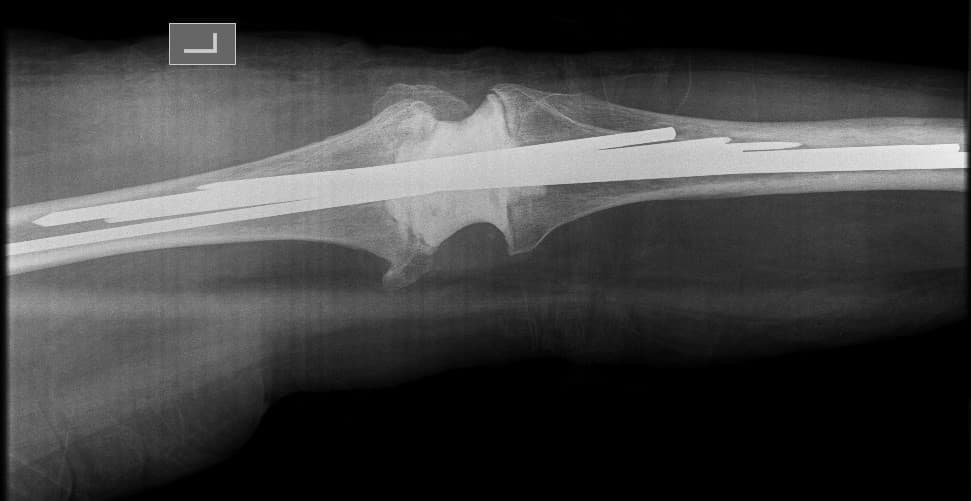

Өвчтөн: С. 57 настай, эрэгтэй

Мэс заслын өмнөх онош: Зүүн дунд чөмөгний түнхний үе орчмын ясны хавдар

Эсийн шинжилгээний хариу: Chondromyxoid fibroma

Шинж тэмдэг: Зүүн түнх, гуя орчим өвддөг, өвдөлт аажим ихсэж байсан, явах зогсох үед өвдөлт нэмэгддэг.

Хөдөлгөөний идэвх: Түнхний үеэр алцайх болон нугалах хөдөлгөөн бага зэрэг хязгаарлагдсан.

Хийгдсэн мэс заслын нэр: Дунд чөмөг-түнхний хавдрын хиймэл үе суулгах мэс засал. Эмнэлэгт хэвтсэн ор хоног 10.

Зураг1. Зүүн дунд чөмөгний түнхний үе орчмын ясны хавдар